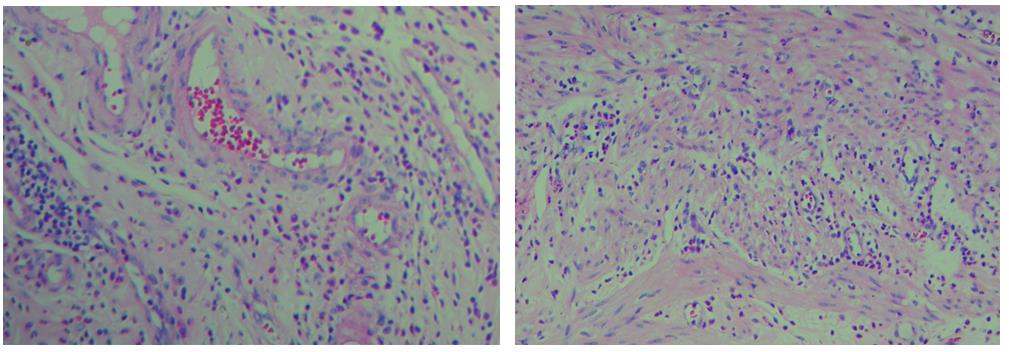

3、色彩鮮艷,核漿紅藍(lán)對(duì)比鮮明,染色效果持久穩(wěn)定,胞核結(jié)構(gòu)清晰

細(xì)胞中的細(xì)胞核由帶負(fù)電荷的酸性物質(zhì)組成,與帶正電荷的堿性染料蘇木素的氧化物三氧化蘇木紅有較強(qiáng)的親和力;而細(xì)胞漿則相反,因含有帶正電荷的堿性物質(zhì)而與帶負(fù)電的酸性染料曙紅Y的親和力較強(qiáng);細(xì)胞或組織切片經(jīng)HE染色后,細(xì)胞核被染成藍(lán)紫色,細(xì)胞漿、紅細(xì)胞、肌纖維、膠原纖維、結(jié)締組織、嗜伊紅顆粒等被染成不同程度的紅色、粉紅色或橙紅色,與藍(lán)色的細(xì)胞核形成鮮明的對(duì)比,因此更易于觀察細(xì)胞或組織中正常成份和病變成份的一般形態(tài)結(jié)構(gòu)。

【實(shí)際染色效果】